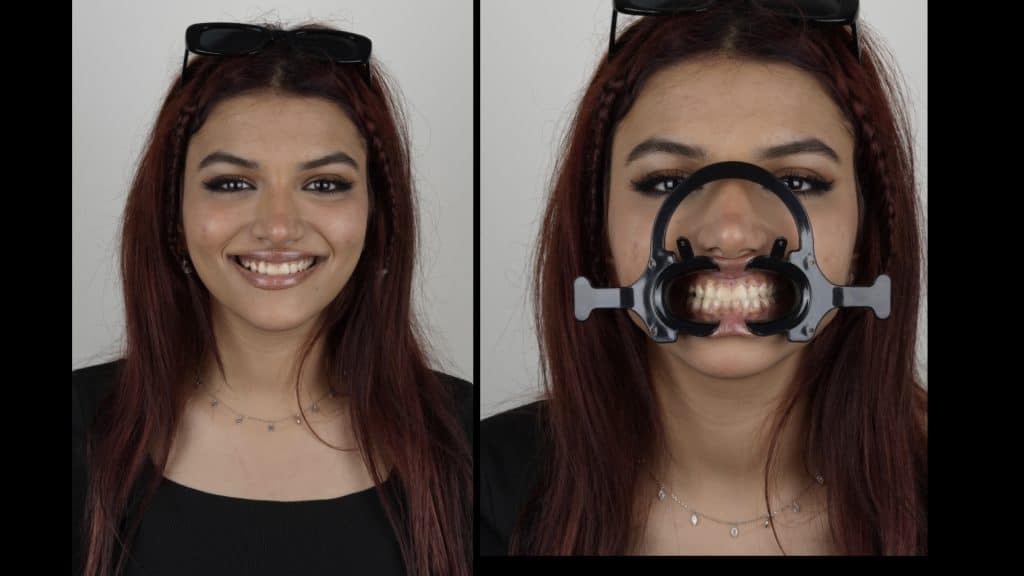

we had to make our first visit to talk only and take impressions and some pictures and videos to the record

We start by make a mock-up to see what are her exceptions and what result she expect.

the smile line and papilla line